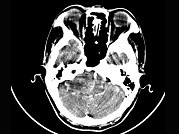

[单选题]女,45岁,右耳听力下降半年余,CT检查如图,最可能诊断为()A.继发性胆脂瘤B.脑膜瘤C.三叉神经瘤D.原发性胆脂瘤E.听神经瘤

[单选题]女,45岁,右耳听力下降半年余,CT检查如图,最可能的诊断是()A.继发性胆脂瘤B.脑膜瘤C.三叉神经瘤D.原发性胆脂瘤E.听神经瘤

[单选题]女,45岁,右耳听力下降半年余,CT检查如图,最可能的诊断是A.继发性胆脂瘤B.脑膜瘤C.三叉神经瘤D.原发性胆脂瘤E.听神经瘤

[单选题]女,45岁,右耳听力下降半年余,CT检查如图,最可能的诊断是( )。A.继发性胆脂瘤B.脑膜瘤C.三叉神经瘤D.原发性胆脂瘤E.听神经瘤